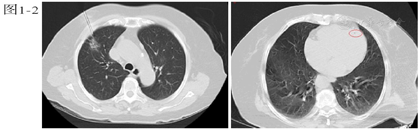

行心电图:窦性心律,T波改变;急查血常规、凝血功能、降钙素原、心肌损伤标记物、BNP未见明显异常。血气分析:酸碱度7.345,二氧化碳分压45.7 mmHg,氧分压74.4 mmHg,乳酸2.1 mmol/L;胸部CT提示:左心室腔可疑气体影(图2)。颅脑CT未见异常,急诊颅脑MRI示:左侧额颞顶枕叶、右侧额顶叶及其皮层下、左侧小脑半球多处新发脑梗死灶(图3a、图4a、图5a)。颈动脉超声:双侧颈动脉内膜增厚。患者同日转入ICU进一步治疗,入室体格检查:T 37.8℃,P 87次/分,R 15次/分,BP 190/109 mmHg,鼻导管吸氧,血氧饱和度98%。浅昏迷状态,GCS评分:E2V2M4,双侧瞳孔等大等圆,直径约2 mm,光反射迟钝。双肺听诊呼吸音清,心脏听诊律齐,未闻及杂音及额外心音。四肢肌张力增高,双侧巴氏征阳性。

本例患者,老年女性,体检发现右肺结节,为明确诊断行CT引导下肺穿刺活检术,术后出现意识改变、肌力下降、肢体抽搐等症状,胸部CT示左心室腔可疑气体影;颅脑MRI示多发新鲜脑梗。双侧颈动脉超声未见狭窄或斑块,既往无房颤病史,暂不支持脑栓塞及脑血栓形成。结合患者穿刺后出现症状、体征及影像学检查,科室内共同讨论后,考虑空气栓塞导致脑梗死不除外。